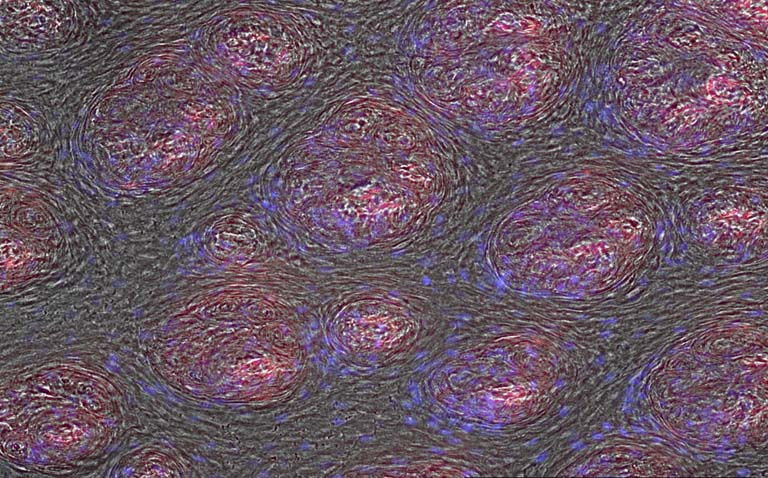

This image is the surface of a freshly harvested pig’s tongue. The blue indicates the cells, the red indicates the nanoparticles that permeate into the tongue. We were examining the permeation of our chemotherapeutic nanoparticle in to the tongue for topical treatment of oral cancer. With oral HPV cancer on the rise, we are determined to develop a local anticancer treatment with very limited toxicity. This treatment can be much more effective than the current treatment and has the potential to significantly reduce the systemic side effects of chemotherapy.